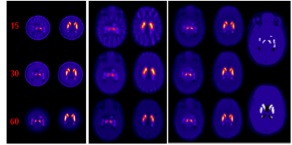

| A. Example XCAT transverse slice multi-pinhole (MPH) collimator noise-free reconstructions through substantia nigra (left) and the caudate and putamen (right) for 15, 30, and 60 angles for VOI over striata. B. Same for low-energy ultra-high-resolution (LEUHR) fan-beam only collimator reconstruction. C. Same for combined reconstruction using MPH and LEUHR fan-beam collimators. D. Matching slices through original XCAT DaTscan source distribution for substantia nigra (top), and caudate and putamen (bottom) with 8:1 striatal to rest of brain concentration ratio, and no activity in the ventricles. Note that separation of caudate and putamen can be seen in combined reconstruction. |